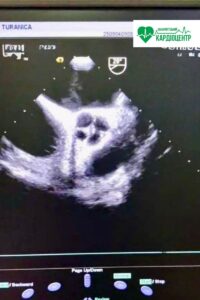

Всесвітній день поширення інформації про вроджені вади серця (ВВС) відзначається щорічно 14 лютого. Ця дата має на меті підвищення обізнаності про серцеві захворювання, з якими народжуються